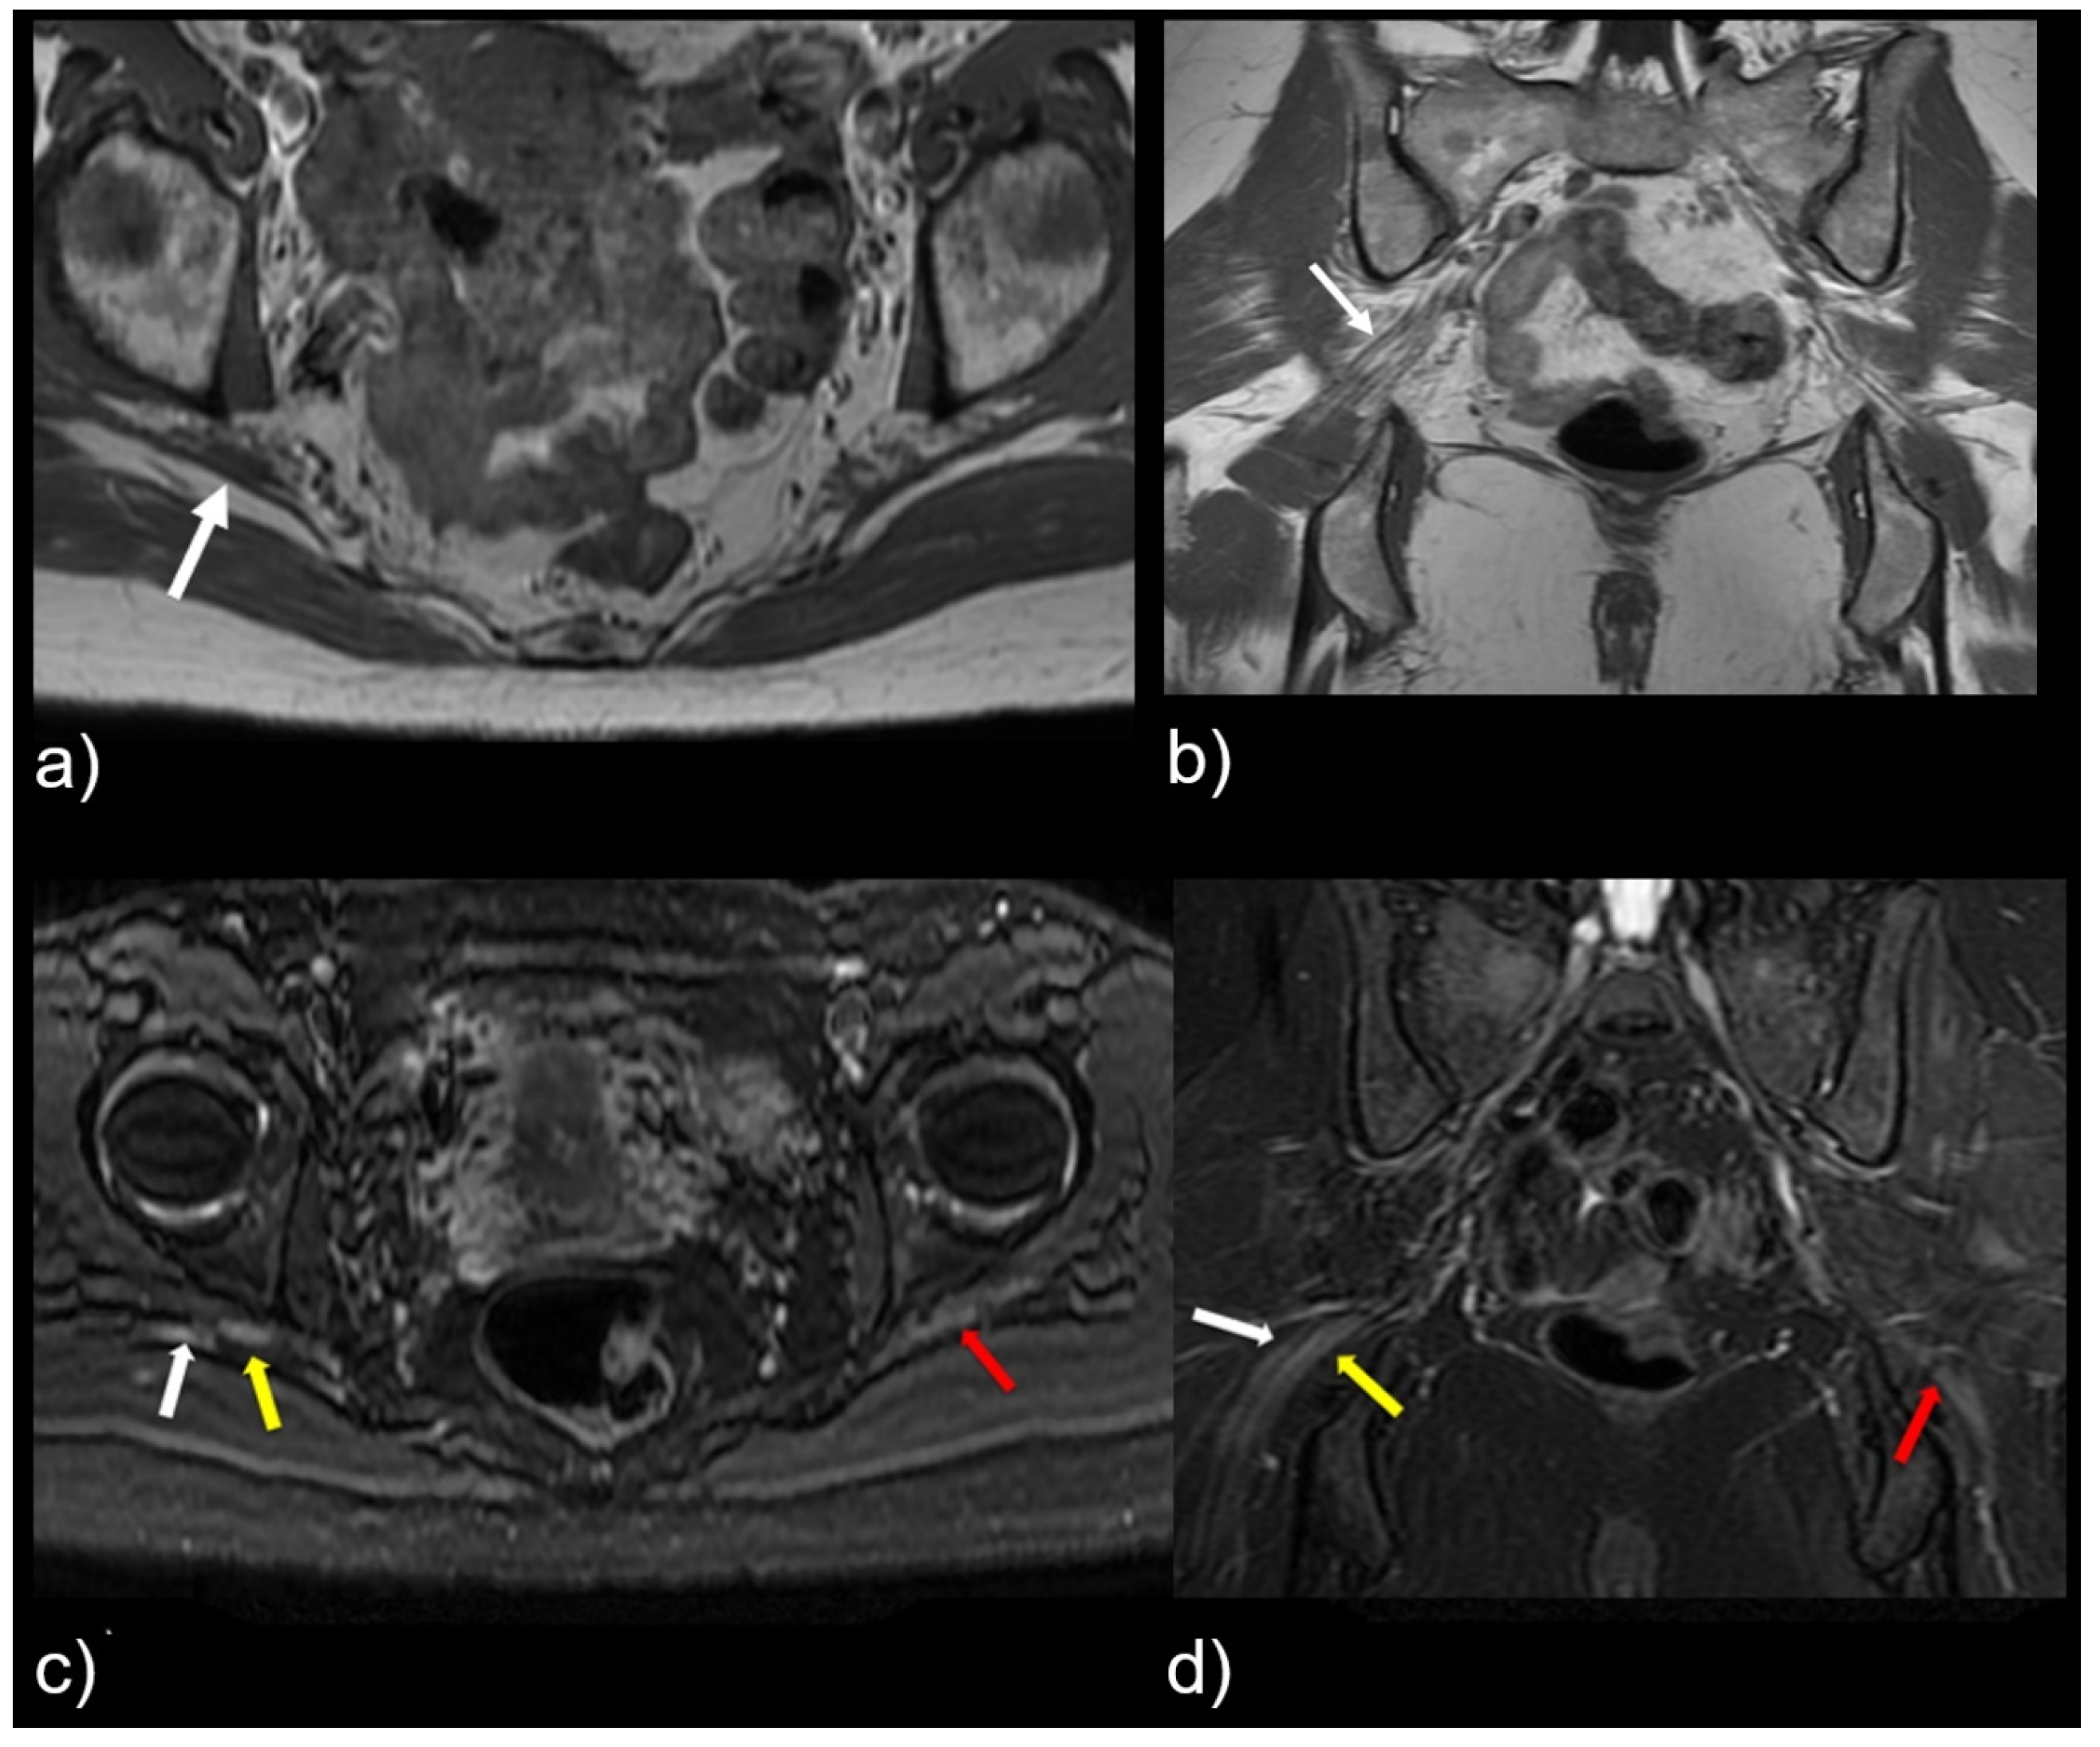

3.2. MR Neurography of the Sciatic Nerves

3.3. Sciatic Nerve Correlation with Findings at MR Neurography